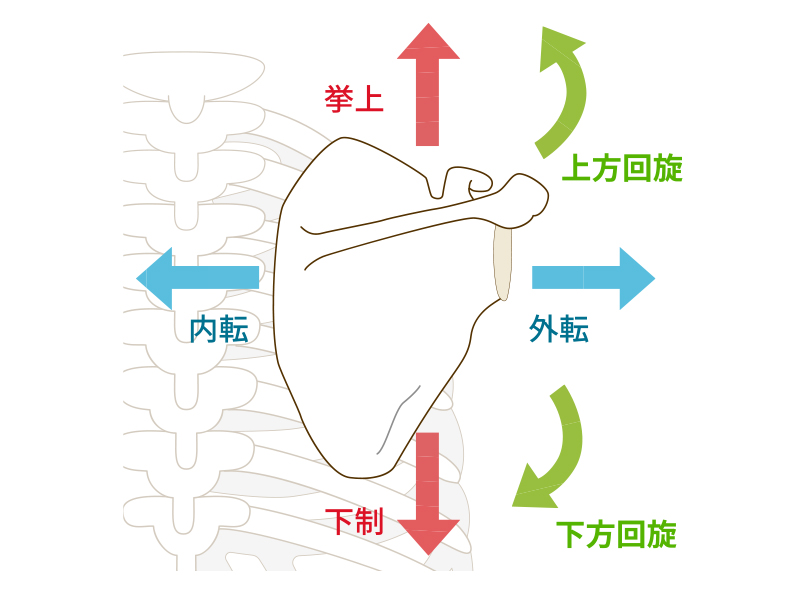

肩甲骨は主に6つの方向に動きます。まず上下方向の動きを「挙上」「下制」と呼びます。頭の方へ上がるのが「挙上」、お尻の方に下がるのが「下制」です。また、左右への動きを「内転」「外転」と呼びます。背骨に近づく動きが「内転」、背骨から離れる動きが「外転」です。さらに、肩甲骨には回転運動もあります。右の肩甲骨で考えると時計回りの回転が「下方回旋」、反時計回りの動きが「上方回旋」です。